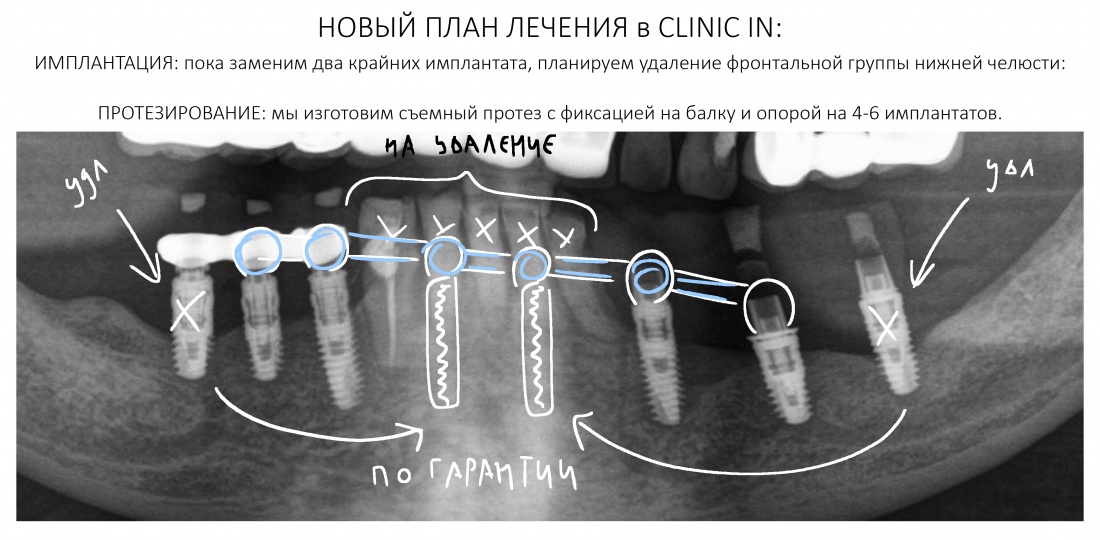

Пациентка того же возраста, что и Елена, начала лечение в нашей клинике около шести лет назад. В течение 2017-2018 гг. мы провели очень большую работу:

Прошло пять лет. Наконец, у Анны (так зовут неуловимую пациентку) появилось время. Но не на продолжение лечения, а для решения возникших стоматологических проблем, которых накопилось немало. Превысив все возможные и невозможные сроки службы временных композитных протезов (которые, кстати, стерлись в ноль, что привело к дисфункции височно-нижнечелюстного сустава), забыв про гигиену полости рта, она свела к нулю всё проведенное ранее лечение и довела установленные имплантаты до состояния, в котором их невозможно нормально протезировать:

Конечно, мы решим эту проблему. В нашей клинике накоплен достаточный опыт лечения периимплантитов и ревизий давно установленных имплантатов. В конце концов, протез можно снова заменить на временный, некоторые имплантаты поменять, а оставшиеся привести всё в порядок.